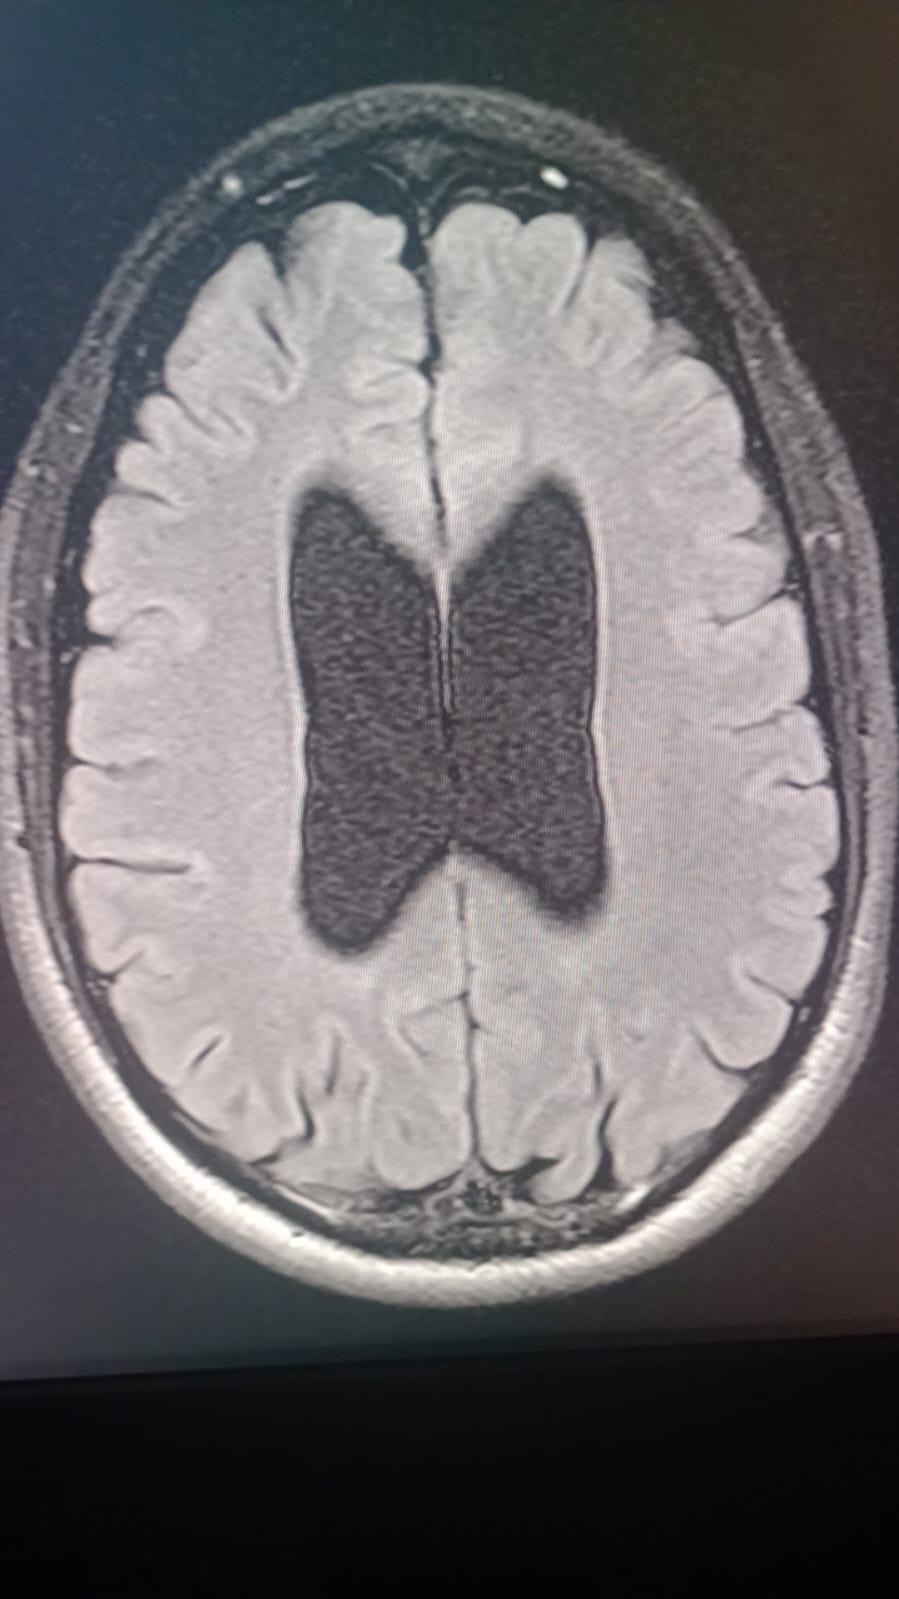

Our dear Cesar Eduardo Rodríguez Ortiz has been fighting seizures since he was just two years old, after suffering a head injury as a baby. Despite years of struggle, his strength and spirit have never faded.

On October 17, 2025, Cesar underwent a major brain surgery to help control his severe epilepsy. By God’s grace, the surgery went well, and he is now beginning his road to recovery.